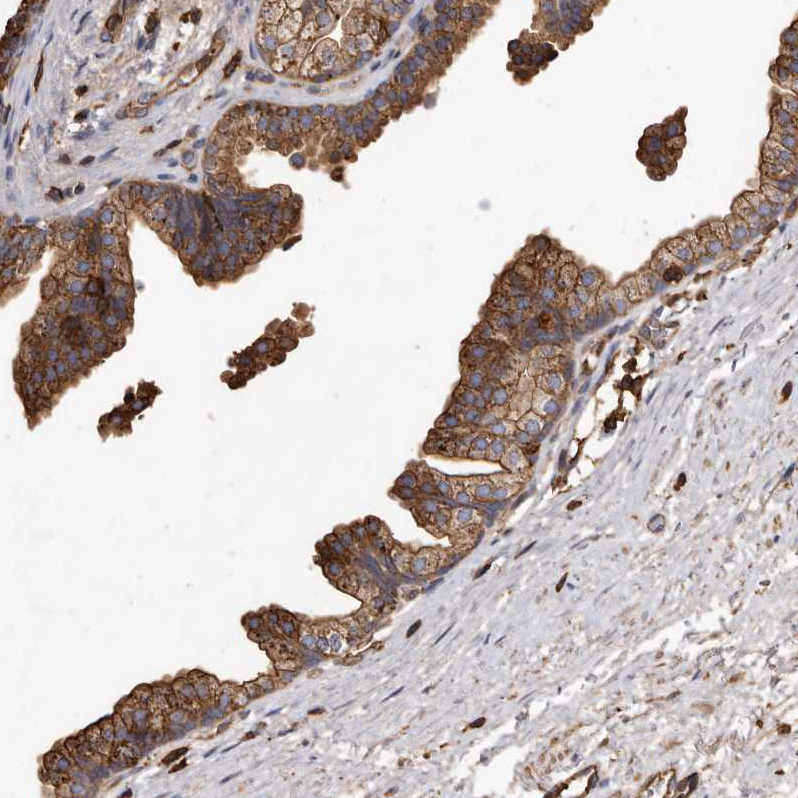

Immunohistochemical staining of human fallopian tube shows moderate membranous and cytoplasmic positivity in glandular cells.